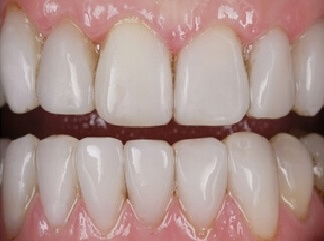

Проблема. На поверхности зубов виден зубной налёт.

Решение. В ходе процедуры с поверхности зубов удаляется зубной налёт с помощью ультразвукового скалера и содоструйного аппарата (Air Flow). В конце процедуры зубы полируются.